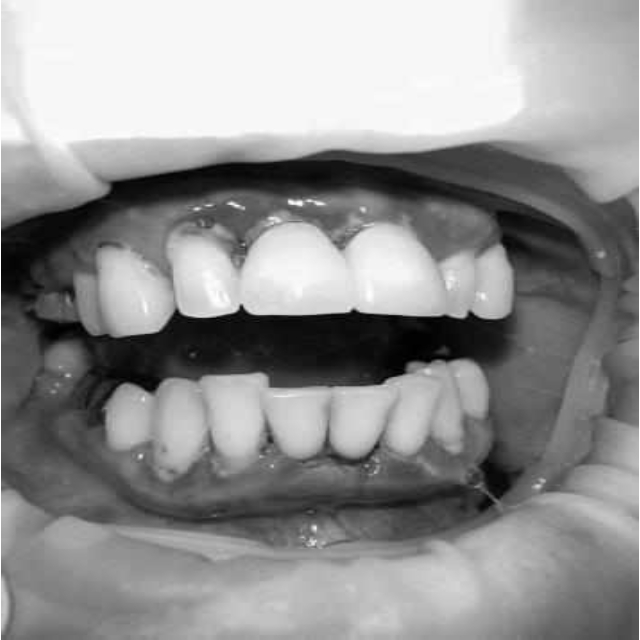

Через 6 месяцев при осмотре выявлен удовлетворительный уровень индивидуальной гигиены, отсутствие участков кровоточивости и гноетечения (рис. 4), пародонтальные карманы уменьшились в размерах (рис. 5). Пациент отмечает значительные улучшения. После стабилизации пародонтологического статуса пациент направлен для дальнейшего ортопедического лечения.

Рис. 4. Динамика результата через 6 месяцев